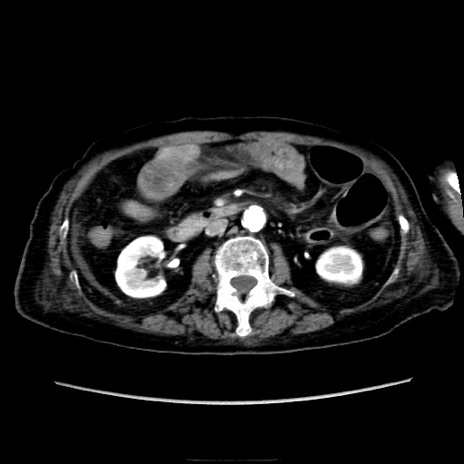

症例40(横断像)

【症例】90歳代女性

【主訴】腹痛・嘔吐

【現病歴】 食欲低下、嘔吐があり昨日他院受診。肺炎と診断され入院となる。入院後より腹部全体に圧痛あり。胃管留置され経過みていたが、症状持続するため、

当院転院となる。

【既往歴】胸椎圧迫骨折、胆石症

【身体所見】腹部:中央に激痛あり、圧痛あり、反跳痛不明

【データ】WBC 17100、CRP 18.82

横断像